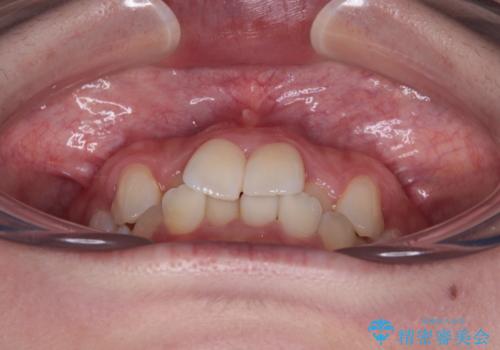

- 上顎前歯のクロスバイトを気にして来院された患者様です。

ワイヤー矯正でもマウスピース矯正でも対応可能でしたが、マウスピースによる自己管理に一切の自信がないとのことで、ワイヤー装置にて矯正治療を行うこととしました。